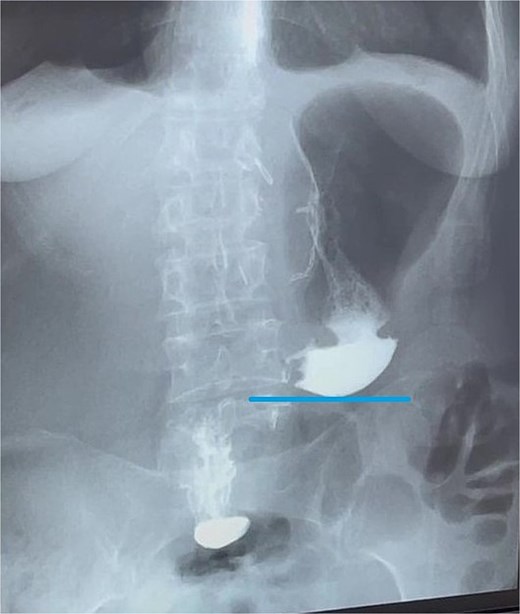

Final surgical pathology report showed scarring deformation of the walls of the antrum of the stomach with signs of chronic inflammation in the muscular coat. No tumor growth was detected (Fig. 5). In 40 examined lymph nodes, there was no tumor growth. The postoperative period was uneventful. On the 3rd day after the operation, a control X-ray examination was performed using a water-soluble contrast agent. It showed that gastric evacuation was timely, and no contrast agent leakage was detected (Fig. 6). The patient was discharged on 7th day after operation with oral nutrition fully restored.

Contrast X-ray study performed on the third postoperative day. The image demonstrates free passage of contrast through a widely patent gastroduodenal (Billroth I) anastomosis without evidence of leakage or obstruction. Line indicates the newly configured lower border of the gastric remnant.